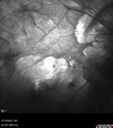

Myopic CNVM Left Eye

80 year old female. VA dropped to 20/125 but improved back up to 20/50 with Vabysmo